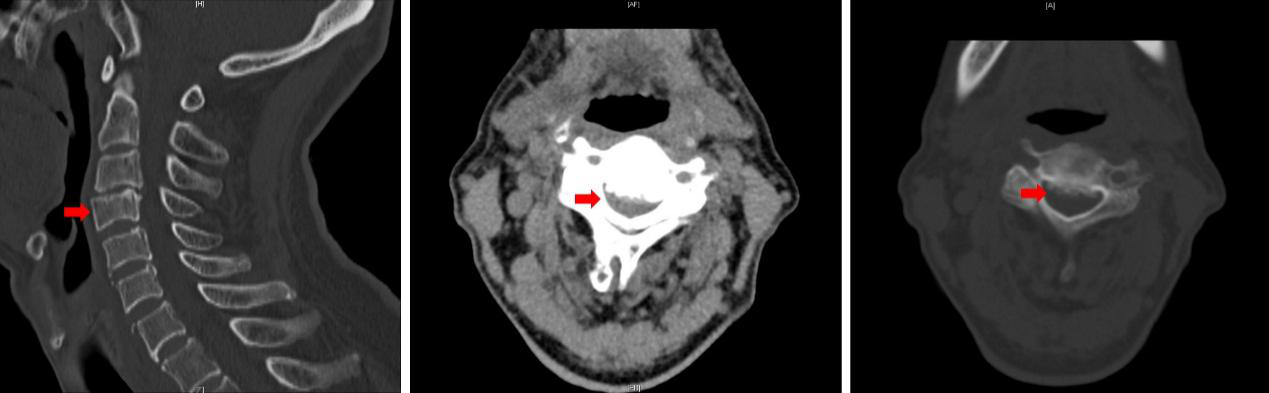

图2 MRI提示C3-7椎间盘突出,C3-4脊髓变性

金爷爷磁共振提示C3-7间盘突出,颈椎管狭窄,但与本次发病有关的是发生脊髓变性和滑脱的C3-4节段。为了保证手术快速且安全的结束,王贵怀教授团队商议本次手术目标为C3-4节段,手术选择颈前入路,损伤小,减压彻底,滑脱复位明确。经过充分的术前准备,麻醉科刘娴医师顺利地为病人进行了全身麻醉,手术由王贵怀教授主刀,孙振兴和张培海医师协助。